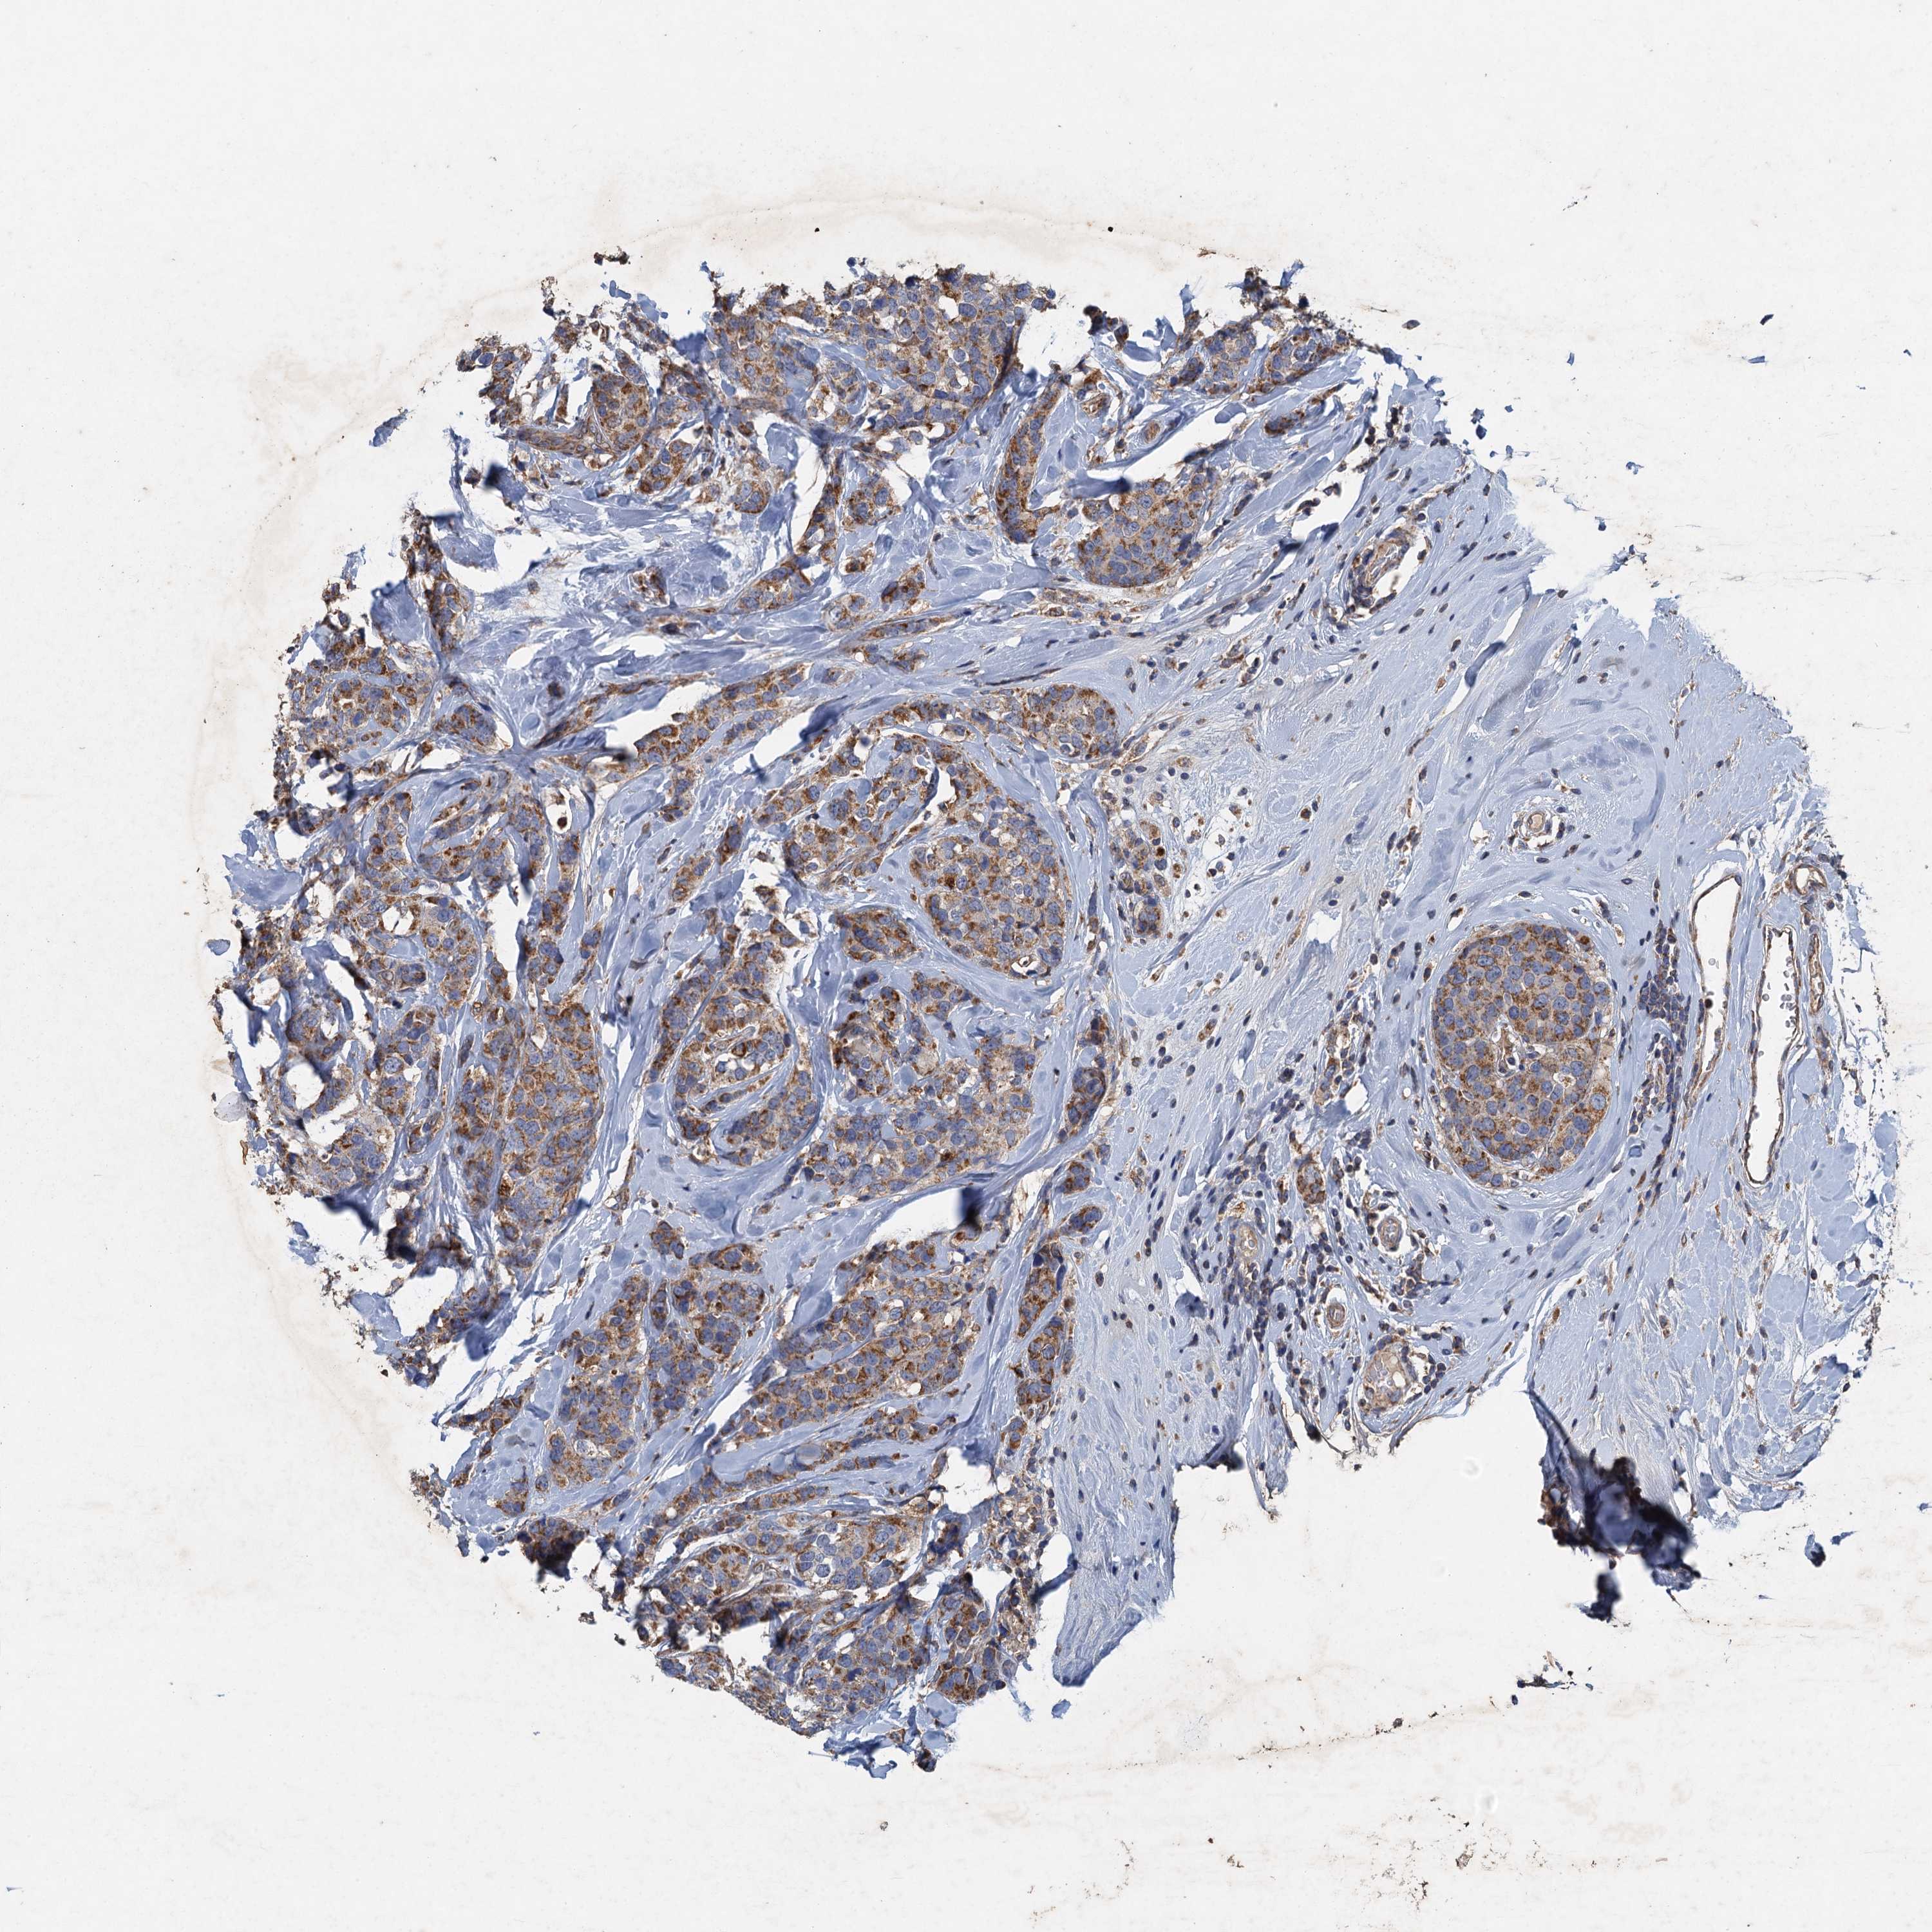

CANCER BREAST CANCER Show tissue menu

BRCA TCGA BRCA VALIDATION PROTEIN EXPRESSION